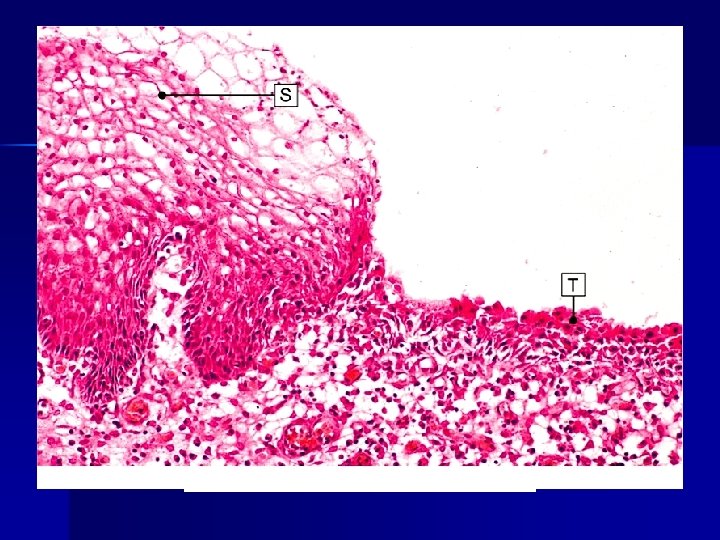

Squamous metaplasia

Anatomy of the cervix